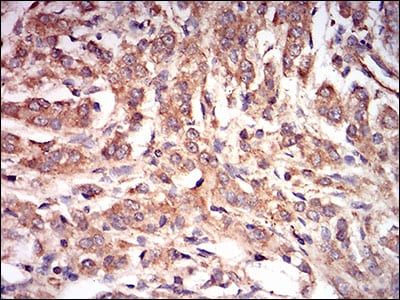

分类: 科研抗体货号: 30601别名: AMPKG应用: IHC反应种属: Human